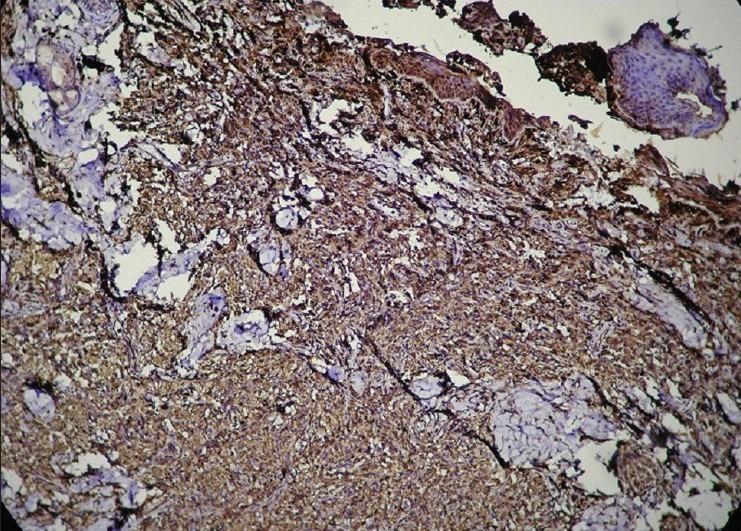

Necrobiotic xanthogranuloma (NXG) is a very rare, progressive variant of non-Langerhans cell histiocytosis. It is known to be associated with multisystem involvement and paraproteinemias. A 65-year-old female presented with chronic, slowly growing, asymptomatic periorbital nodules. The lesions had recurred after local excision elsewhere. No systemic involvement or paraproteinemias were detected. A provisional diagnosis of isolated cutaneous NXG was made which was confirmed by histopathology and immunohistochemistry staining. The lesions were surgically excised with excellent cosmetic and functional results. There was no recurrence over a period of 9 months. To our knowledge, this is the second case of NXG reported from India and the first without any systemic manifestations.